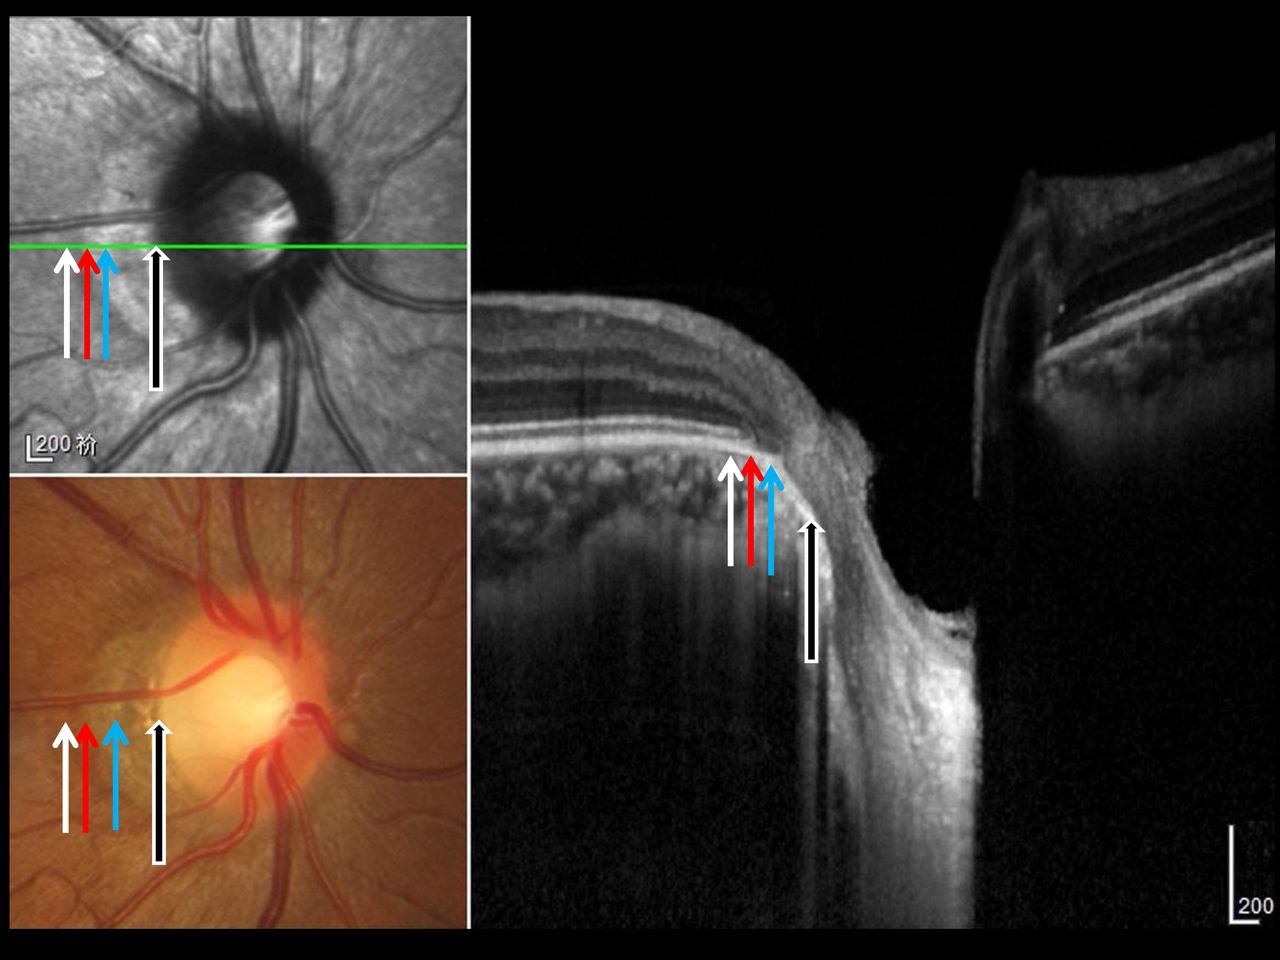

이와 반대로 Gamma zone PPA라고 하여, 최근 새로운 개념이 나오고 있습니다

이는 새로운 영역이 발견된 것이아니라 기존의 Beta zone PPA 의 영역들을 세분화하여 구분한것입니다.

Beta zone PPA는 망막색소상피(RPE)층이 없고 그 아래의 맥락막 모세혈관들이 위축되어,

맥락막의 굵은 혈관들이나 공막이 보이는 부분을 의미합니다.

이부분을 광학 단층촬영으로 유심히 관찰하면, Bruch membrane 이라는 브루크막이 있는 부분이 있고 없는 부분이 있습니다.

Beta zone PPA 중에서 Bruch membrane 이 있는 곳을 새롭게 Beta zone 이라고 정의하고 있고,

Beta zone PPA중에서 Bruch membrane 이 없는 곳을 Gamma zone이라고 명명하고 있습니다.

그럼 Alpha zone 이 가장 바깥쪽에 위치하고 그 안쪽에 Beta zone , 가장 안쪽에 Gamam zone 이 위치하는 형태가 됩니다.

이렇게 정의한 Beta zone 은 기존의 동일하게 시신경 섬유의 손상이 큰쪽에서 더 너비가 넓은 양상을 보이는데,

반대로 Gamma zone 은 Gamma zone 이 넓은 환자에서 녹내장의 진행이 적다거나, 시신경 보호 효과를 하는 것으로 알려져 있어, 최근 연구들의 대상이 되고 있습니다.